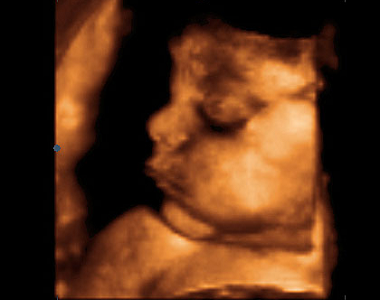

Obrázek 1: Plod starý 22 týdnů (24. týden těhotenství). Plod se vznáší v plodové vodě, je obalen plodovými obaly. Děložní dutina již zcela vymizela, sliznice srostla s amniochoriovou blánou. Pupečníkem je plod připojen k placentě. V děložním hrdle je hlenová zátka.